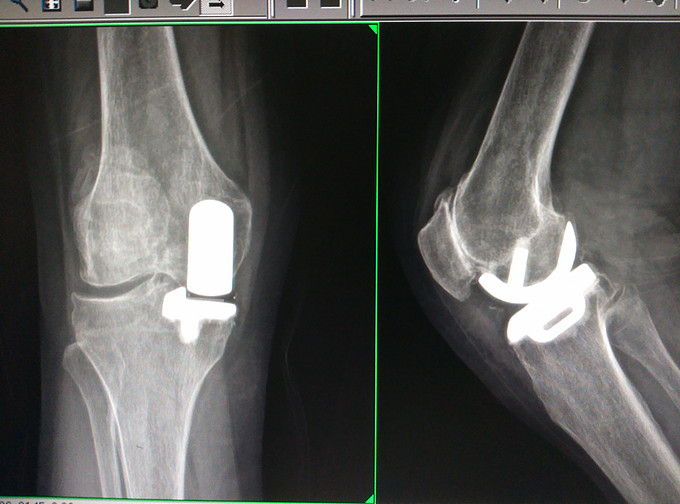

膝关节骨性关节炎,内侧间室退行性病变。 膝关节单髁置换术。

术后康复顺利,术后6周已能正常行走。步态较健康人群无明显异常。 目前单髁置换术的适应症有所扩大。除了伴有髌骨外侧疼痛的髌股关节退变,髌股关节退变已非UKA的禁忌症。置换掉正常的外侧间室 实在可惜。各位同道单髁置换术的开展情况如何?